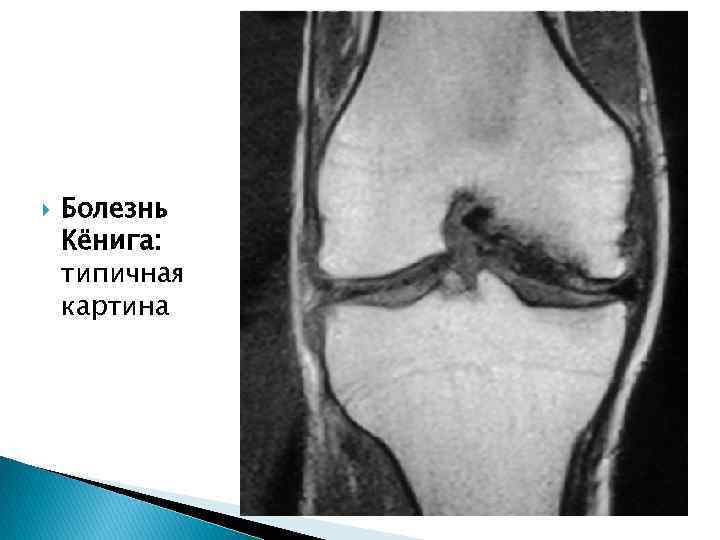

Болезнь Кенига или рассекающий (отсекающий) остеохондроз (остехондрит) - заболевание при котором участок хряща, покрывающий кости, постепенно отслаивается и может даже полностью отделиться от кости. Если участок хряща отделится от кости, то он станет свободно перемещаться по коленному суставу, мешая движениям. Представьте, что в коробке передач автомобиля свободно болтается, например, гайка. Конечно же, в таком случае нормальная работа механизма невозможна. Отделившийся от кости участок хряща называют свободным внутрисуставным телом или суставной мышью

Ограниченный асептический остеонекроз (болезнь Кенига) В I стадии происходит формирование очага остеонекроза. При рентгенологическом исследовании определяется в типичном месте (внутренний мыщелок бедра) очаг просветления с расположенным внутри костным телом, которое дает плотную бесструктурную тень. Замыкательная пластинка сохранена. II стадия – диссекция. На рентгенограммах определяется нарушение целостности замыкательной пластинки, более широкая полоса просветления между некротическим телом и «нишей» . III стадия - неполное отделение некротического тела. Рентгенологически: дефект медиального мыщелка бедра, на уровне которого в проекции сустава выявляется суставная мышь. IV стадия - свободной суставной мыши. Дефект медиального мыщелка бедра, и в полости сустава свободная суставная мышь.

Болезнь Кёнига: типичная картина